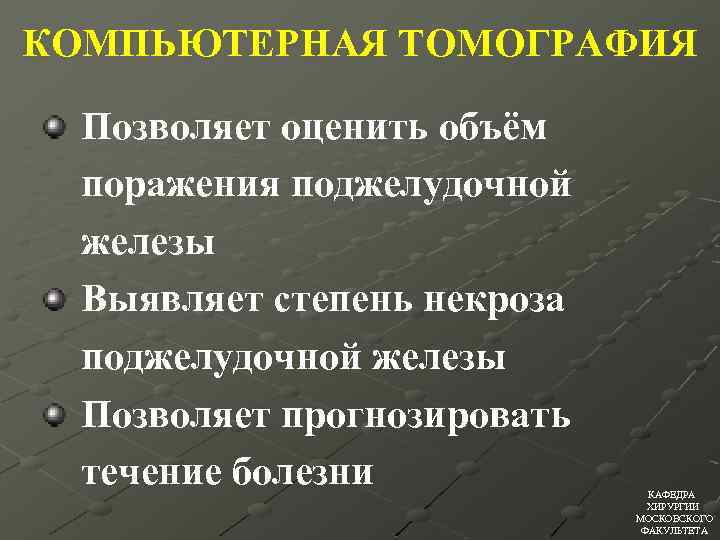

КОМПЬЮТЕРНАЯ ТОМОГРАФИЯ Позволяет оценить объём поражения поджелудочной железы Выявляет степень некроза поджелудочной железы Позволяет прогнозировать течение болезни КАФЕДРА ХИРУРГИИ МОСКОВСКОГО ФАКУЛЬТЕТА

КОМПЬЮТЕРНАЯ ТОМОГРАФИЯ Позволяет оценить объём поражения поджелудочной железы Выявляет степень некроза поджелудочной железы Позволяет прогнозировать течение болезни КАФЕДРА ХИРУРГИИ МОСКОВСКОГО ФАКУЛЬТЕТА

КОМПЬЮТЕРНАЯ ТОМОГРАФИЯ • А. Нормальные размеры и контрастирование железы • B. Увеличение в размерах • C. Перипанкреатит с воспалительными изменениями жировой ткани • D. С + наличие жидкости в переднем параренальном пространстве • E. D + наличие жидкости в сальниковой сумке Balthazar КАФЕДРА ХИРУРГИИ МОСКОВСКОГО ФАКУЛЬТЕТА

КОМПЬЮТЕРНАЯ ТОМОГРАФИЯ • А. Нормальные размеры и контрастирование железы • B. Увеличение в размерах • C. Перипанкреатит с воспалительными изменениями жировой ткани • D. С + наличие жидкости в переднем параренальном пространстве • E. D + наличие жидкости в сальниковой сумке Balthazar КАФЕДРА ХИРУРГИИ МОСКОВСКОГО ФАКУЛЬТЕТА

КОМПЬЮТЕРНАЯ ТОМОГРАФИЯ • А=0 • В=1 • С=2 • D=3 • Е=4 • Отсутствие некроза=0 • Некроз до 13 поджелудочной железы=2 • Некроз 50% поджелудочной железы=4 • Некроз >50% поджелудочной железы=6 КАФЕДРА ХИРУРГИИ МОСКОВСКОГО ФАКУЛЬТЕТА

КОМПЬЮТЕРНАЯ ТОМОГРАФИЯ • А=0 • В=1 • С=2 • D=3 • Е=4 • Отсутствие некроза=0 • Некроз до 13 поджелудочной железы=2 • Некроз 50% поджелудочной железы=4 • Некроз >50% поджелудочной железы=6 КАФЕДРА ХИРУРГИИ МОСКОВСКОГО ФАКУЛЬТЕТА

КОМПЬЮТЕРНАЯ ТОМОГРАФИЯ • 1 -2 балла – вероятность тяжелого панкреатита тяжелыми осложнениями невозможна • 3 -6 баллов – вероятность тяжелого панкреатита с тяжелыми осложнениями мала • 7 -10 баллов – вероятность тяжелого панкреатита с тяжелыми осложнениями 92%, летальность – 17% КАФЕДРА ХИРУРГИИ МОСКОВСКОГО ФАКУЛЬТЕТА

КОМПЬЮТЕРНАЯ ТОМОГРАФИЯ • 1 -2 балла – вероятность тяжелого панкреатита тяжелыми осложнениями невозможна • 3 -6 баллов – вероятность тяжелого панкреатита с тяжелыми осложнениями мала • 7 -10 баллов – вероятность тяжелого панкреатита с тяжелыми осложнениями 92%, летальность – 17% КАФЕДРА ХИРУРГИИ МОСКОВСКОГО ФАКУЛЬТЕТА